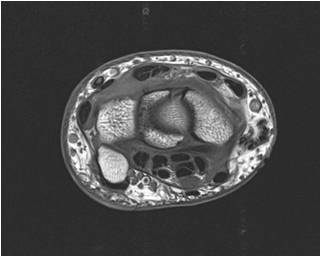

Distal Arm and Elbow

Identify: Radial nerve, brachial artery, biceps tendon, basilic vein, cephalic vein, brachialis, Brachioradialis, olecranon process, oleranon fossa, ulnar nerve, median cubital vein, ulnar groove, pronator teres, flexor carpi ulnaris.